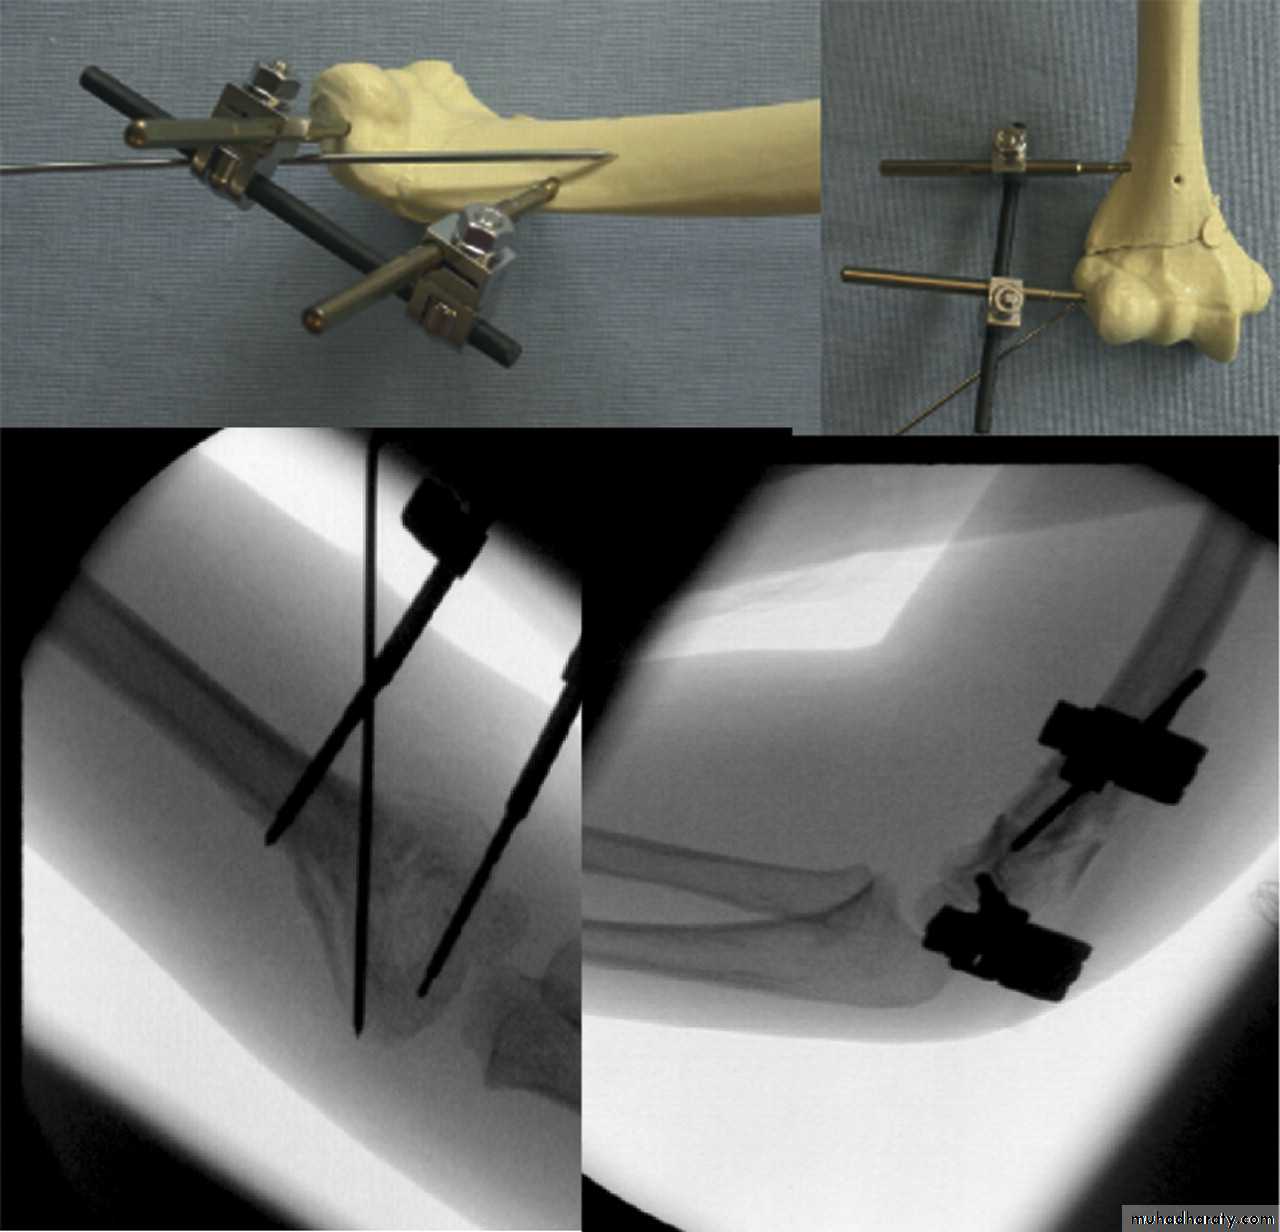

What is the place for an external fixatorif any?

Screws in proximal

and distal fragmentsSingle pin to control

rotation

Reported useful

to manipulatethe fragments

The place for an external fixator

May be effective

with

comminution of